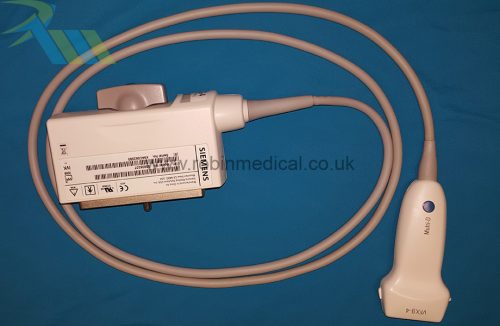

The probe functions as intended and the condition is exactly as shown in images.